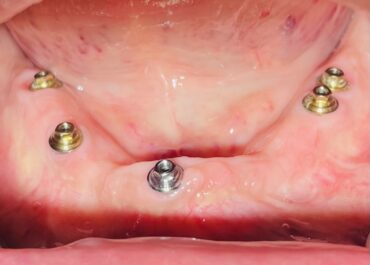

L’implantologia dentale rappresenta una soluzione moderna e efficace per la sostituzione dei denti mancanti, con numerosi vantaggi sia estetici che funzionali. Tuttavia, come ogni procedura medica, comporta dei rischi che è importante conoscere e considerare. In questo articolo, esamineremo i principali rischi associati a questa pratica, con l’obiettivo di fornire una panoramica chiara e informativa per coloro che stanno valutando questa opzione.

Un altro rischio significativo è la possibilità che l’impianto non si integri correttamente con l’osso, fenomeno noto come mancata osteointegrazione. Questo può avvenire per vari motivi, tra cui una scarsa qualità o quantità dell’osso, l’uso di materiali di scarsa qualità, o condizioni mediche preesistenti come il diabete. Quando l’osteointegrazione non avviene, l’impianto può diventare instabile e, in casi estremi, potrebbe essere necessario rimuoverlo.

Anche quando l’intervento ha successo, esiste il rischio che l’impianto fallisca nel lungo periodo. Questo può accadere per una serie di motivi, tra cui una scarsa igiene orale, fumo, bruxismo (digrignamento dei denti) o malattie gengivali. Per prevenire il fallimento a lungo termine, è essenziale mantenere un’ottima igiene orale e sottoporsi a controlli regolari dal dentista.